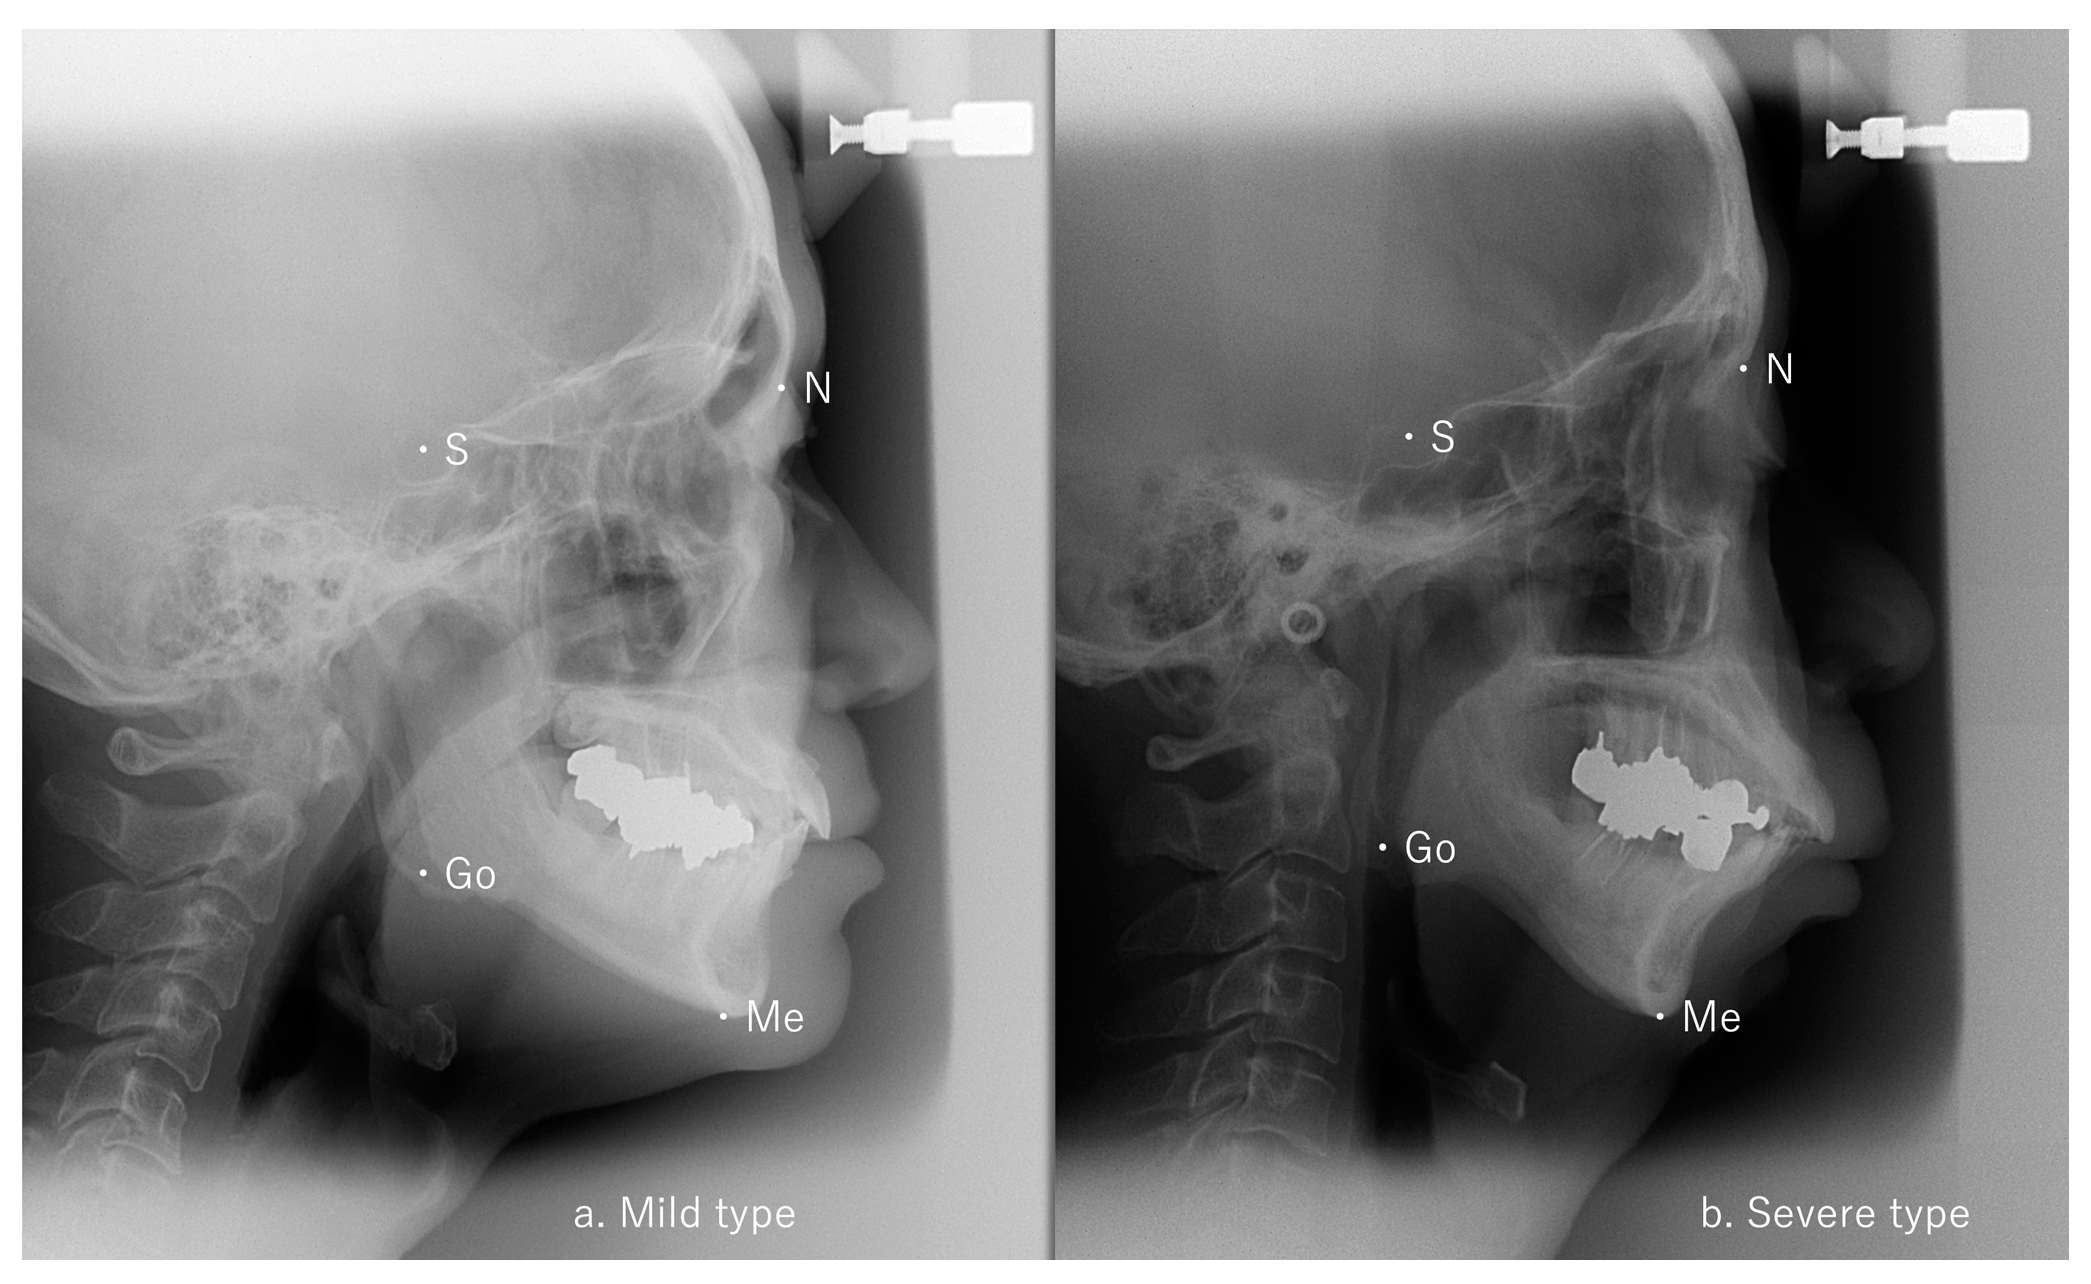

A significant difference in Go-Me/S-N was identified between the mild and moderate groups (p < 0.05) and between the mild and severe groups (p < 0.05) but not between the moderate and severe groups (Table 1). Representative cephalometric analyses of the mild and severe groups are shown in Figure 2. No differences among the three groups were seen for any of the five factors from the Ricketts analysis (Table 1).

Figure 2.

Lateral cephalometric radiographs. (a) Mild AHI patient: S-Go/N-Me 65.6% and Go-Me/S-N 102.1%, (b) severe AHI patient: S-Go/N-Me 67.5% and Go-Me/S-N 99.8%, AHI: apnea–hypopnea index.